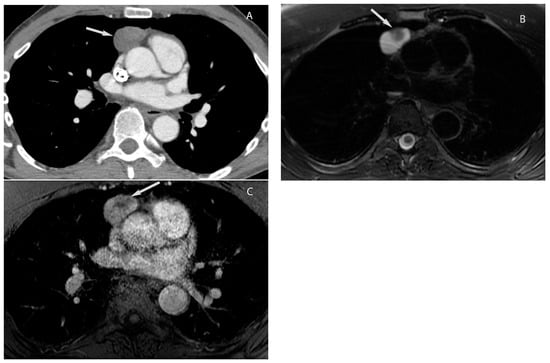

5. Thymic Epithelial Neoplasms